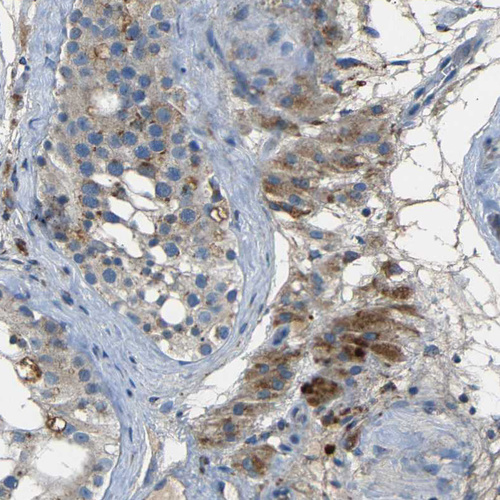

Immunohistochemical staining of human testis shows moderate granular cytoplasm positivity in leydig cells and cells in seminiferous ducts.